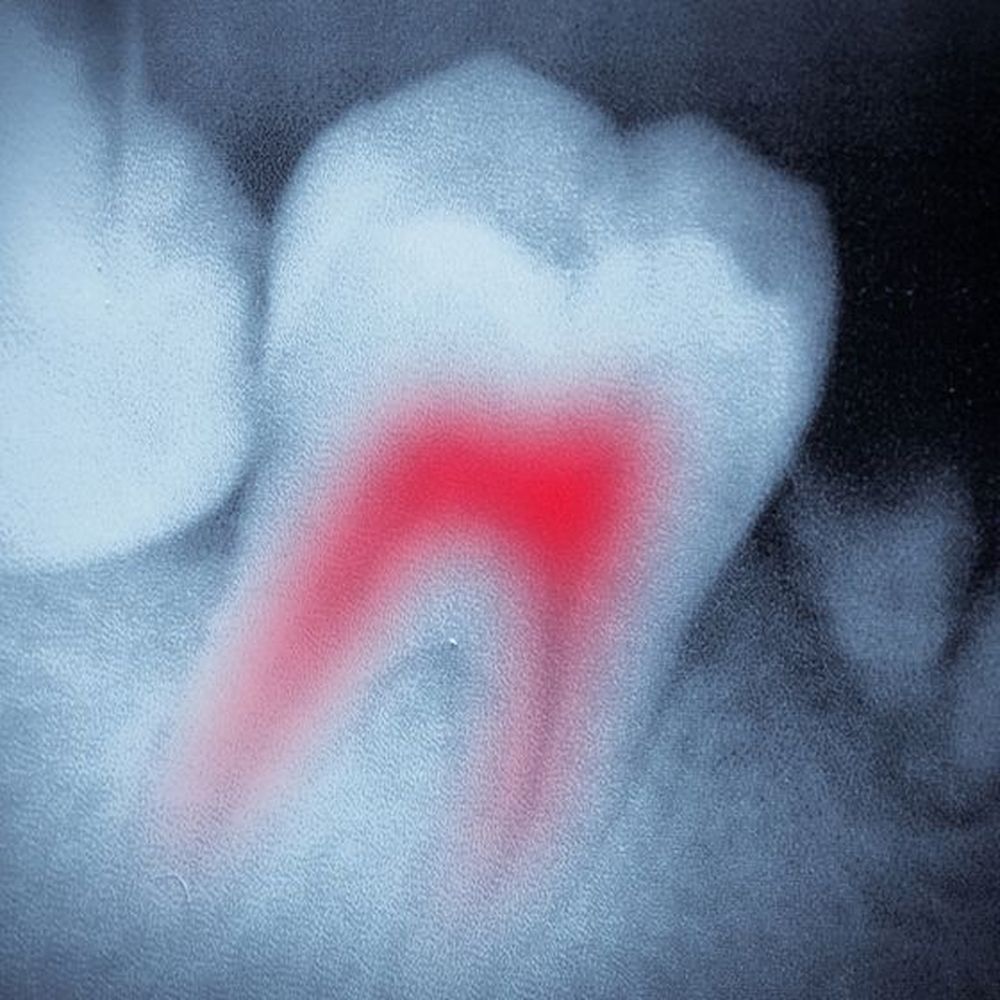

Root Canal Therapy